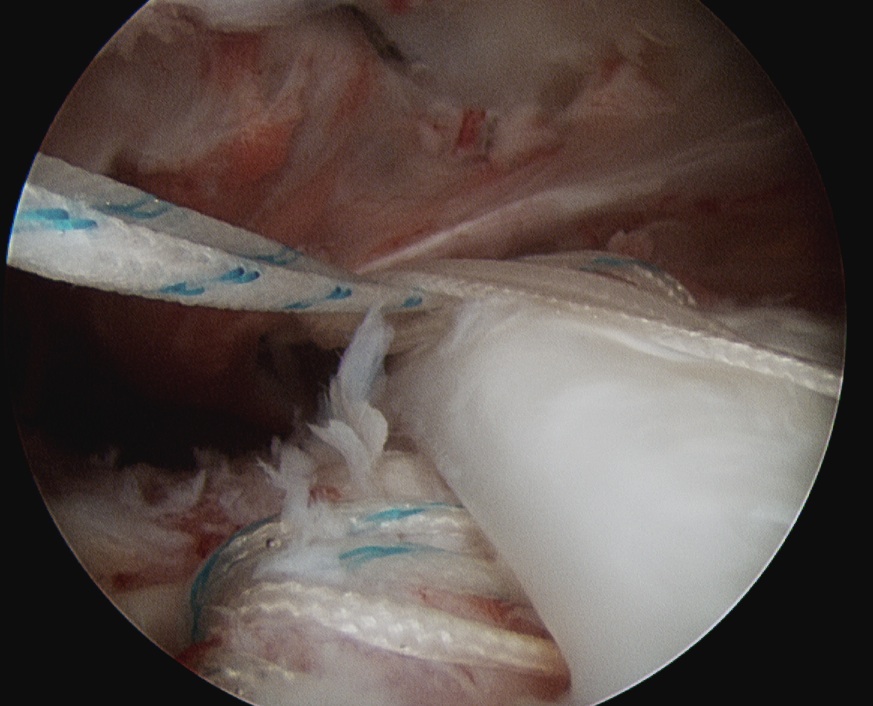

- pass sutures with suture passer

- tie